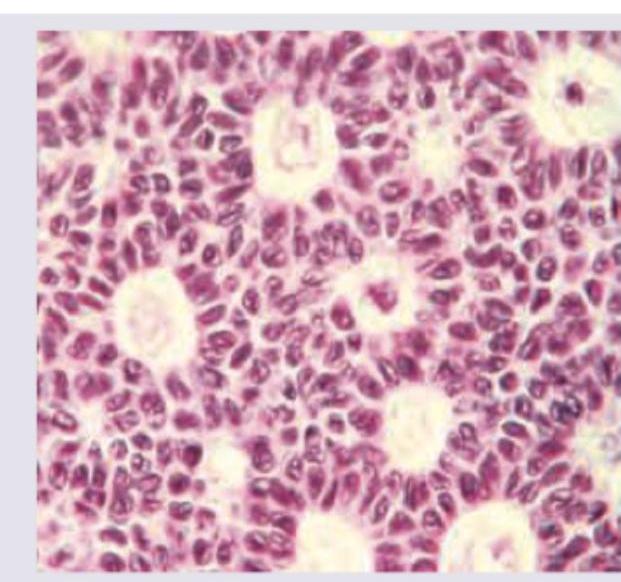

A 6-year-old girl with precocious puberty was found to have an ovarian tumour, which was resected laparoscopically. Histopathological slides were prepared. What is the diagnosis?

Explanation: ***Granulosa cell tumour*** - Granulosa cell tumours are the most common **estrogen-producing ovarian tumours** in children, leading to **precocious puberty** [2]. - Histologically, they often show **Call-Exner bodies** and a coffee-bean nuclear groove. - These tumors can occur at any age and all cases are potentially malignant [2]. *Arrhenoblastoma* - Arrhenoblastomas are **androgen-producing tumours** that cause **virilization** (e.g., hirsutism, clitoromegaly), not precocious puberty [3]. - They are typically composed of Sertoli and Leydig cells. *Endodermal sinus tumour* - Endodermal sinus tumours (yolk sac tumours) are **germ cell tumours** that produce **alpha-fetoprotein (AFP)**. - They are highly malignant and do not typically cause precocious puberty. *Thecoma* - Thecomas are benign ovarian tumours that can produce **estrogen**, but they are **less common** than granulosa cell tumours as a cause of precocious puberty in this age group [2]. - They are composed primarily of lipid-laden spindle cells [2]. **References:** [1] Kumar V, Abbas AK, et al.. Robbins and Cotran Pathologic Basis of Disease. 9th ed. The Female Genital Tract, pp. 1036-1037. [2] Cross SS. Underwood's Pathology: A Clinical Approach. 6th ed. Common Clinical Problems From Female Genital Tract Disease, pp. 481-482. [3] Kumar V, Abbas AK, et al.. Robbins and Cotran Pathologic Basis of Disease. 9th ed. The Female Genital Tract, pp. 1037-1038.